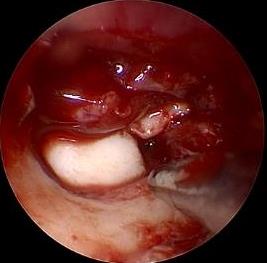

摘要:目的 探讨耳内镜下耳屏软骨-软骨膜鼓膜修补术后的短期疗效。方法 回顾性分析2019年9月-2022年8月该院收治的78例鼓膜穿孔患者的临床资料,患者均采用耳内镜下鼓膜修补术。术后随访3个月,观察鼓膜形态和穿孔愈合情况,记录内镜图像、干耳时间、术前术后听力及耳鸣情况,以及外耳道狭窄等并发症的发生率。结果 术后3个月,鼓膜穿孔愈合率为97.44%(76/78),愈合良好,平均气导听阈较术前明显改善,气骨导间距较术前明显缩小,耳鸣较术前明显改善,差异均有统计学意义(P<0.05)。干耳时间为(4.21±1.12)周。术后出现肉芽5例,再穿孔2例,真菌感染2例,术腔感染、耳屏感染、外耳道狭窄和切口瘢痕各1例,所有患者术后均未发生面神经麻痹和感音神经性聋等严重并发症。结论 耳内镜下耳屏软骨-软骨膜鼓膜修补术是一种安全、有效的手术方法。根据术后愈合规律、内镜下鼓膜和外耳道形态特征,可为鼓膜修补术后正常中耳转归和并发症的诊疗,提供临床参考。